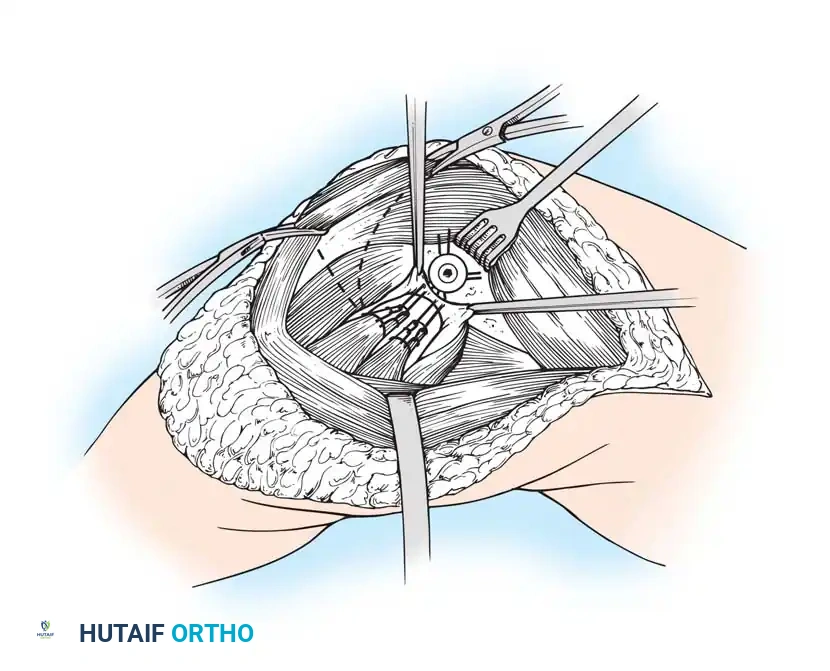

The Subvastus ("Southern") Approach

In an effort to reduce patellofemoral complications and expedite the return of quadriceps function, alternative methods of exposure have been developed. The subvastus approach, advocated by Hofmann, Plaster, and Murdock, avoids violating the extensor mechanism.

- The same anterior midline skin incision is used.

- The proximal retinacular incision is performed by incising the superficial fascia overlying the vastus medialis.

- Bluntly mobilize the distal medial border of the vastus medialis posteriorly to the medial intermuscular septum.

- Lift the origin of the vastus medialis off the medial intermuscular septum to approximately 10 cm proximal to the adductor tubercle, staying distal to the aperture for the femoral vessels.

- Incise the synovium and dislocate the entire extensor mechanism laterally.

Advocates of the subvastus approach note that leaving the extensor mechanism intact results in a more rapid return of quadriceps strength, preserves the vascularity to the patella (specifically the supreme genicular artery), decreases postoperative pain, and reduces the need for lateral retinacular release. However, exposure can be severely limited in obese patients, highly muscular individuals, or those with previous knee surgeries.